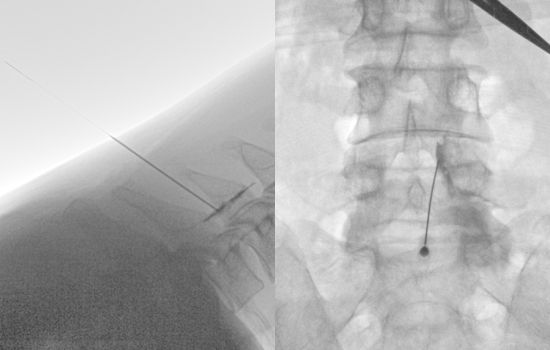

신경차단술(척추신경 주사 치료)

디스크, 협착증이 발생하면 신경을 자극하는 염증이 생깁니다.

허리, 목 또는 다리 통증을 느끼게 되는데원인이 되는 곳에 특수 바늘로 약물을 주입해 염증을 제거하고 통증을 가라앉힙니다.